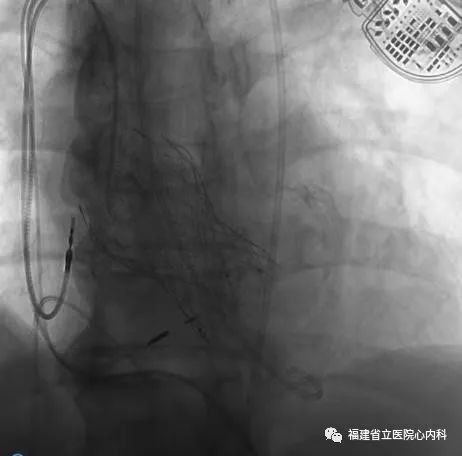

病例2

该病例是TYPE0型二叶瓣,瓣叶增厚伴极重度钙化,同时升主动脉增宽且为横位心,导致输送系统通过主动脉弓及瓣膜口难度明显增加,而且瓣上存在限制结构,瓣膜移位风险高,术中手术团队默契配合,输送系统顺利通过主动脉弓及狭窄的瓣口,Venus A-L26瓣膜定位精准释放,达到术前预期锚定位置,最终效果佳。

瓣环

窦部

球囊预扩张

植入L26瓣膜